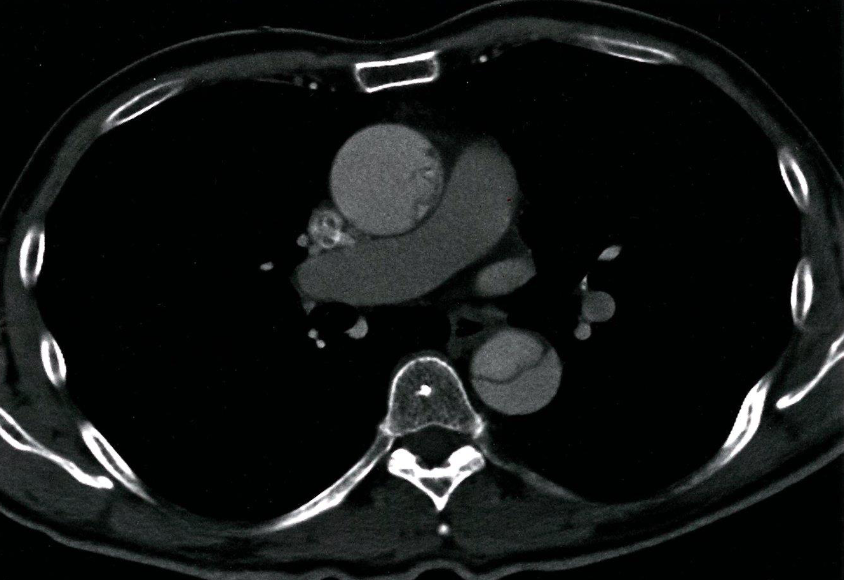

- CT thorax (with contrast; axial view)

- A mucosal flap can be seen dividing the lumen of the ascending and descending aorta.

- This radiological appearance confirms an aortic dissection.